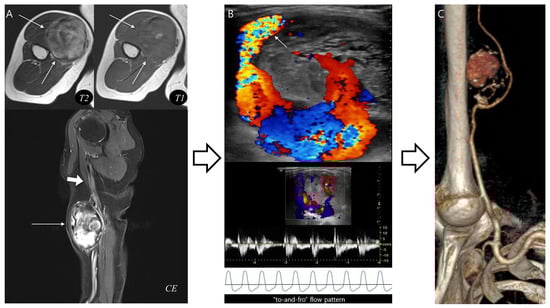

Pseudoaneurysm Versus Chronic Expanding Hematoma on MRI: Hematoma-like Lesions with Distinct Therapeutic Strategies

by

Seul Ki Lee, Jun-Ho Kim and Jee-Young Kim

Biomedicines 2025, 13(11), 2834; https://doi.org/10.3390/biomedicines13112834 - 20 Nov 2025

Background/Objectives: Pseudoaneurysm and chronic expanding hematoma (CEH) are uncommon soft tissue lesions that can mimic hematoma or hemorrhagic tumors on magnetic resonance imaging (MRI). Because treatment strategies differ, accurate differentiation is important. This study aimed to compare MRI characteristics of pseudoaneurysm and CEH

Background/Objectives: Pseudoaneurysm and chronic expanding hematoma (CEH) are uncommon soft tissue lesions that can mimic hematoma or hemorrhagic tumors on magnetic resonance imaging (MRI). Because treatment strategies differ, accurate differentiation is important. This study aimed to compare MRI characteristics of pseudoaneurysm and CEH and identify distinguishing imaging features. Methods: We retrospectively reviewed 12 patients diagnosed between June 2010 and June 2023 with pseudoaneurysm (n = 6) or CEH (n = 6). Patient demographics, lesion depth, and size were compared. MRI features were evaluated for morphology, internal characteristics, pulsatile artifact, and involvement of adjacent structures. Results: Pseudoaneurysms were consistently located in the muscle layer, whereas CEHs were predominantly found in the subcutaneous fat layer (83.3%, p = 0.015). CEHs were significantly larger than pseudoaneurysms (13.5 ± 3.9 cm vs. 6.1 ± 3.3 cm, p = 0.005). Pseudoaneurysm more frequently exhibited ovoid morphology (100%), central flow void on T1WI and T2WI (100%), inner peripheral high SI on T1WI (83.3%), and neurovascular bundle involvement (100%) (all p < 0.05), while CEHs demonstrated multilobular morphology (100%) and internal septations (83.3%) (p < 0.05). Conclusions: Lesion location, size, morphology, central flow void, inner peripheral high T1 signal, septation, and neurovascular involvement enables reliable MRI differentiation between pseudoaneurysm and CEH, guiding accurate diagnosis and guiding appropriate management.